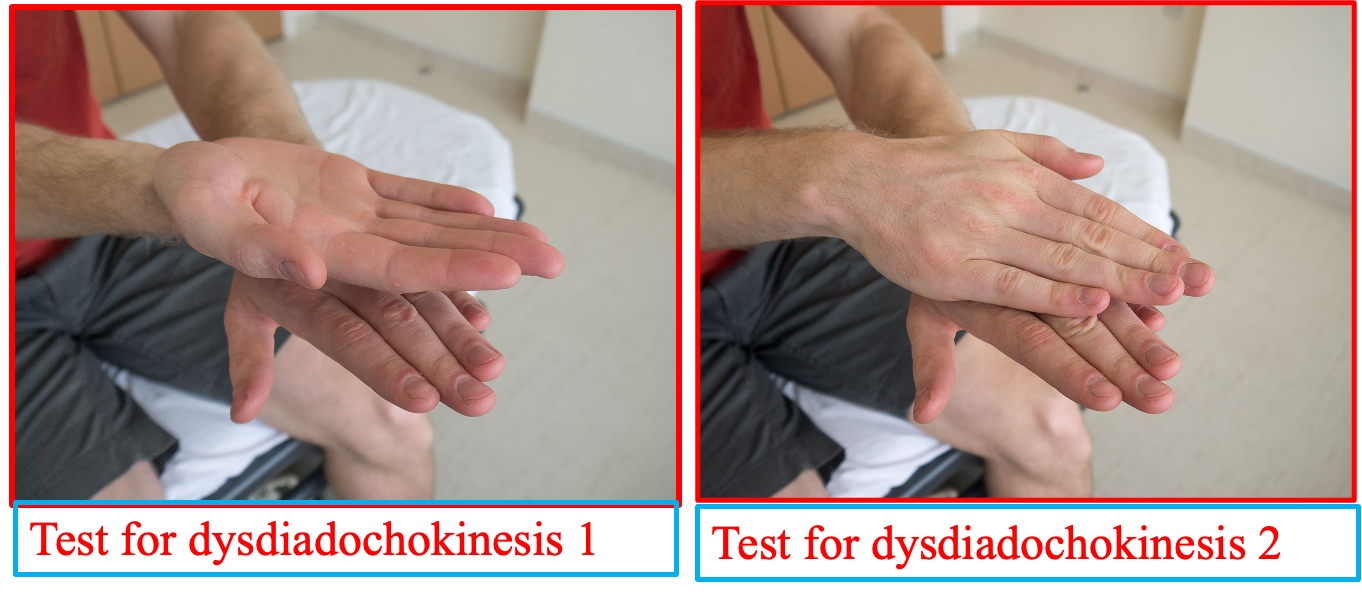

A) Rapid Alternating movements

- Diadochokinesia = ability to perform RAM

- Dysdiadochokinesis = slow, irregular, clumsy movements

Cerebellar function (dysdiadochokinesis)

Co-ordination: Test for dysdiadochokinesis by showing the patient how to clap by alternating the palmar and dorsal surfaces of the hand. Ask them to do this as fast as possible and repeat the test with the other hand.